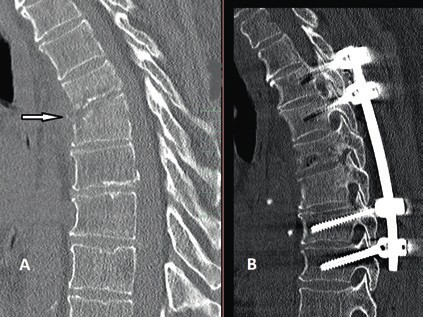

Prinzipiell richtet sich die Entscheidung, welche operative Versorgung durchgeführt wird, nach Ausmaß und Art der Verletzung. Für die Stabilisierung der dorsalen Säule reicht im Falle einer stabilen ventralen Säule die dorsale Instrumentierung aus. Hier gewährleisten dorsale Pedikelschrauben, die mit einem Stab verbunden sind, eine gute Wiederherstellung der Stabilität (Abb. 2). Im Falle einer instabilen ventralen Säule ist hingegen eine Implantation von Wirbelkörperersatz und eine dorsoventrale Segmentversteifung indiziert (Abb. 3). Die entwickelten minimalinvasiven Techniken – zum Beispiel die transkutane Pedikelschraubenimplantation oder der Wirbelkörperersatz durch endoskopische Thorakotomie – haben dazu geführt, dass das Wundgebiet und die operationsbedingte Gewebeschädigung reduziert werden und somit eine Belastungsreduktion für den Körper erzielt wird. Dieser Aspekt ist insbesondere bei älteren Patienten mit multiplen Begleiterkrankungen von Vorteil. Im Falle einer osteoporotischen Wirbelsäule werden die implantierten Pedikelschrauben zementiert (Abb. 4). Auch hier erlaubt die Entwicklung fenestrierter Schrauben eine optimale Möglichkeit der Zementapplikation.

Ziel einer operativen Therapie in beiden Fällen ist die Entlastung der neuralen Strukturen. Auch in diesem Bereich wurden Operationstechniken entwickelt, die mit minimalinvasiven „Schlüsselloch-“ oder mikroskopischen Methoden eine gute Entlastung erreichen. Diese Entwicklung der operativen Methoden spiegelt sich in der Literatur wider. So finden wir im Jahre 1949 die Laminektomie als führende Operationstechnik zur Rückenmarkentlastung; hingegen wird diese Technik heutzutage nicht mehr favorisiert. Es werden heute moderne entlastende Operationstechniken mit deutlich weniger Gewebszerstörung angewendet, etwa die mikrochirurgische oder endoskopische Dekompression mittels Laminotomie oder die Crossover-Technik, die eine beidseitige Entlastung durch einen einseitigen Zugang erlaubt. Auch Laminoplastie und Duraerweiterungsplastik sind im Laufe dieser Entwicklungsrichtung weniger invasiv geworden und werden bei älteren Patienten zunehmend eingesetzt (Abb. 5).